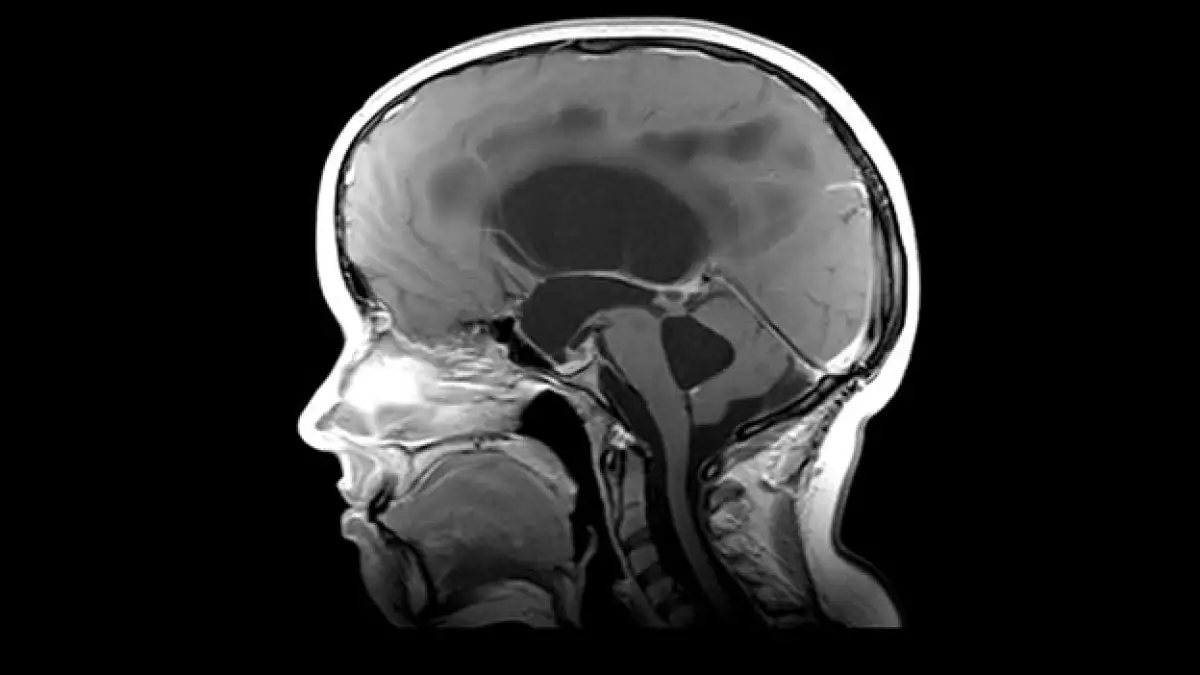

Un ruso aquejado de atrofia muscular espinal (AME), una grave enfermedad genética que ataca las neuronas motoras, quiere someterse a una pionera operación en la que su cabeza sería trasplantada a un cuerpo sano uniéndola por la espina dorsal.